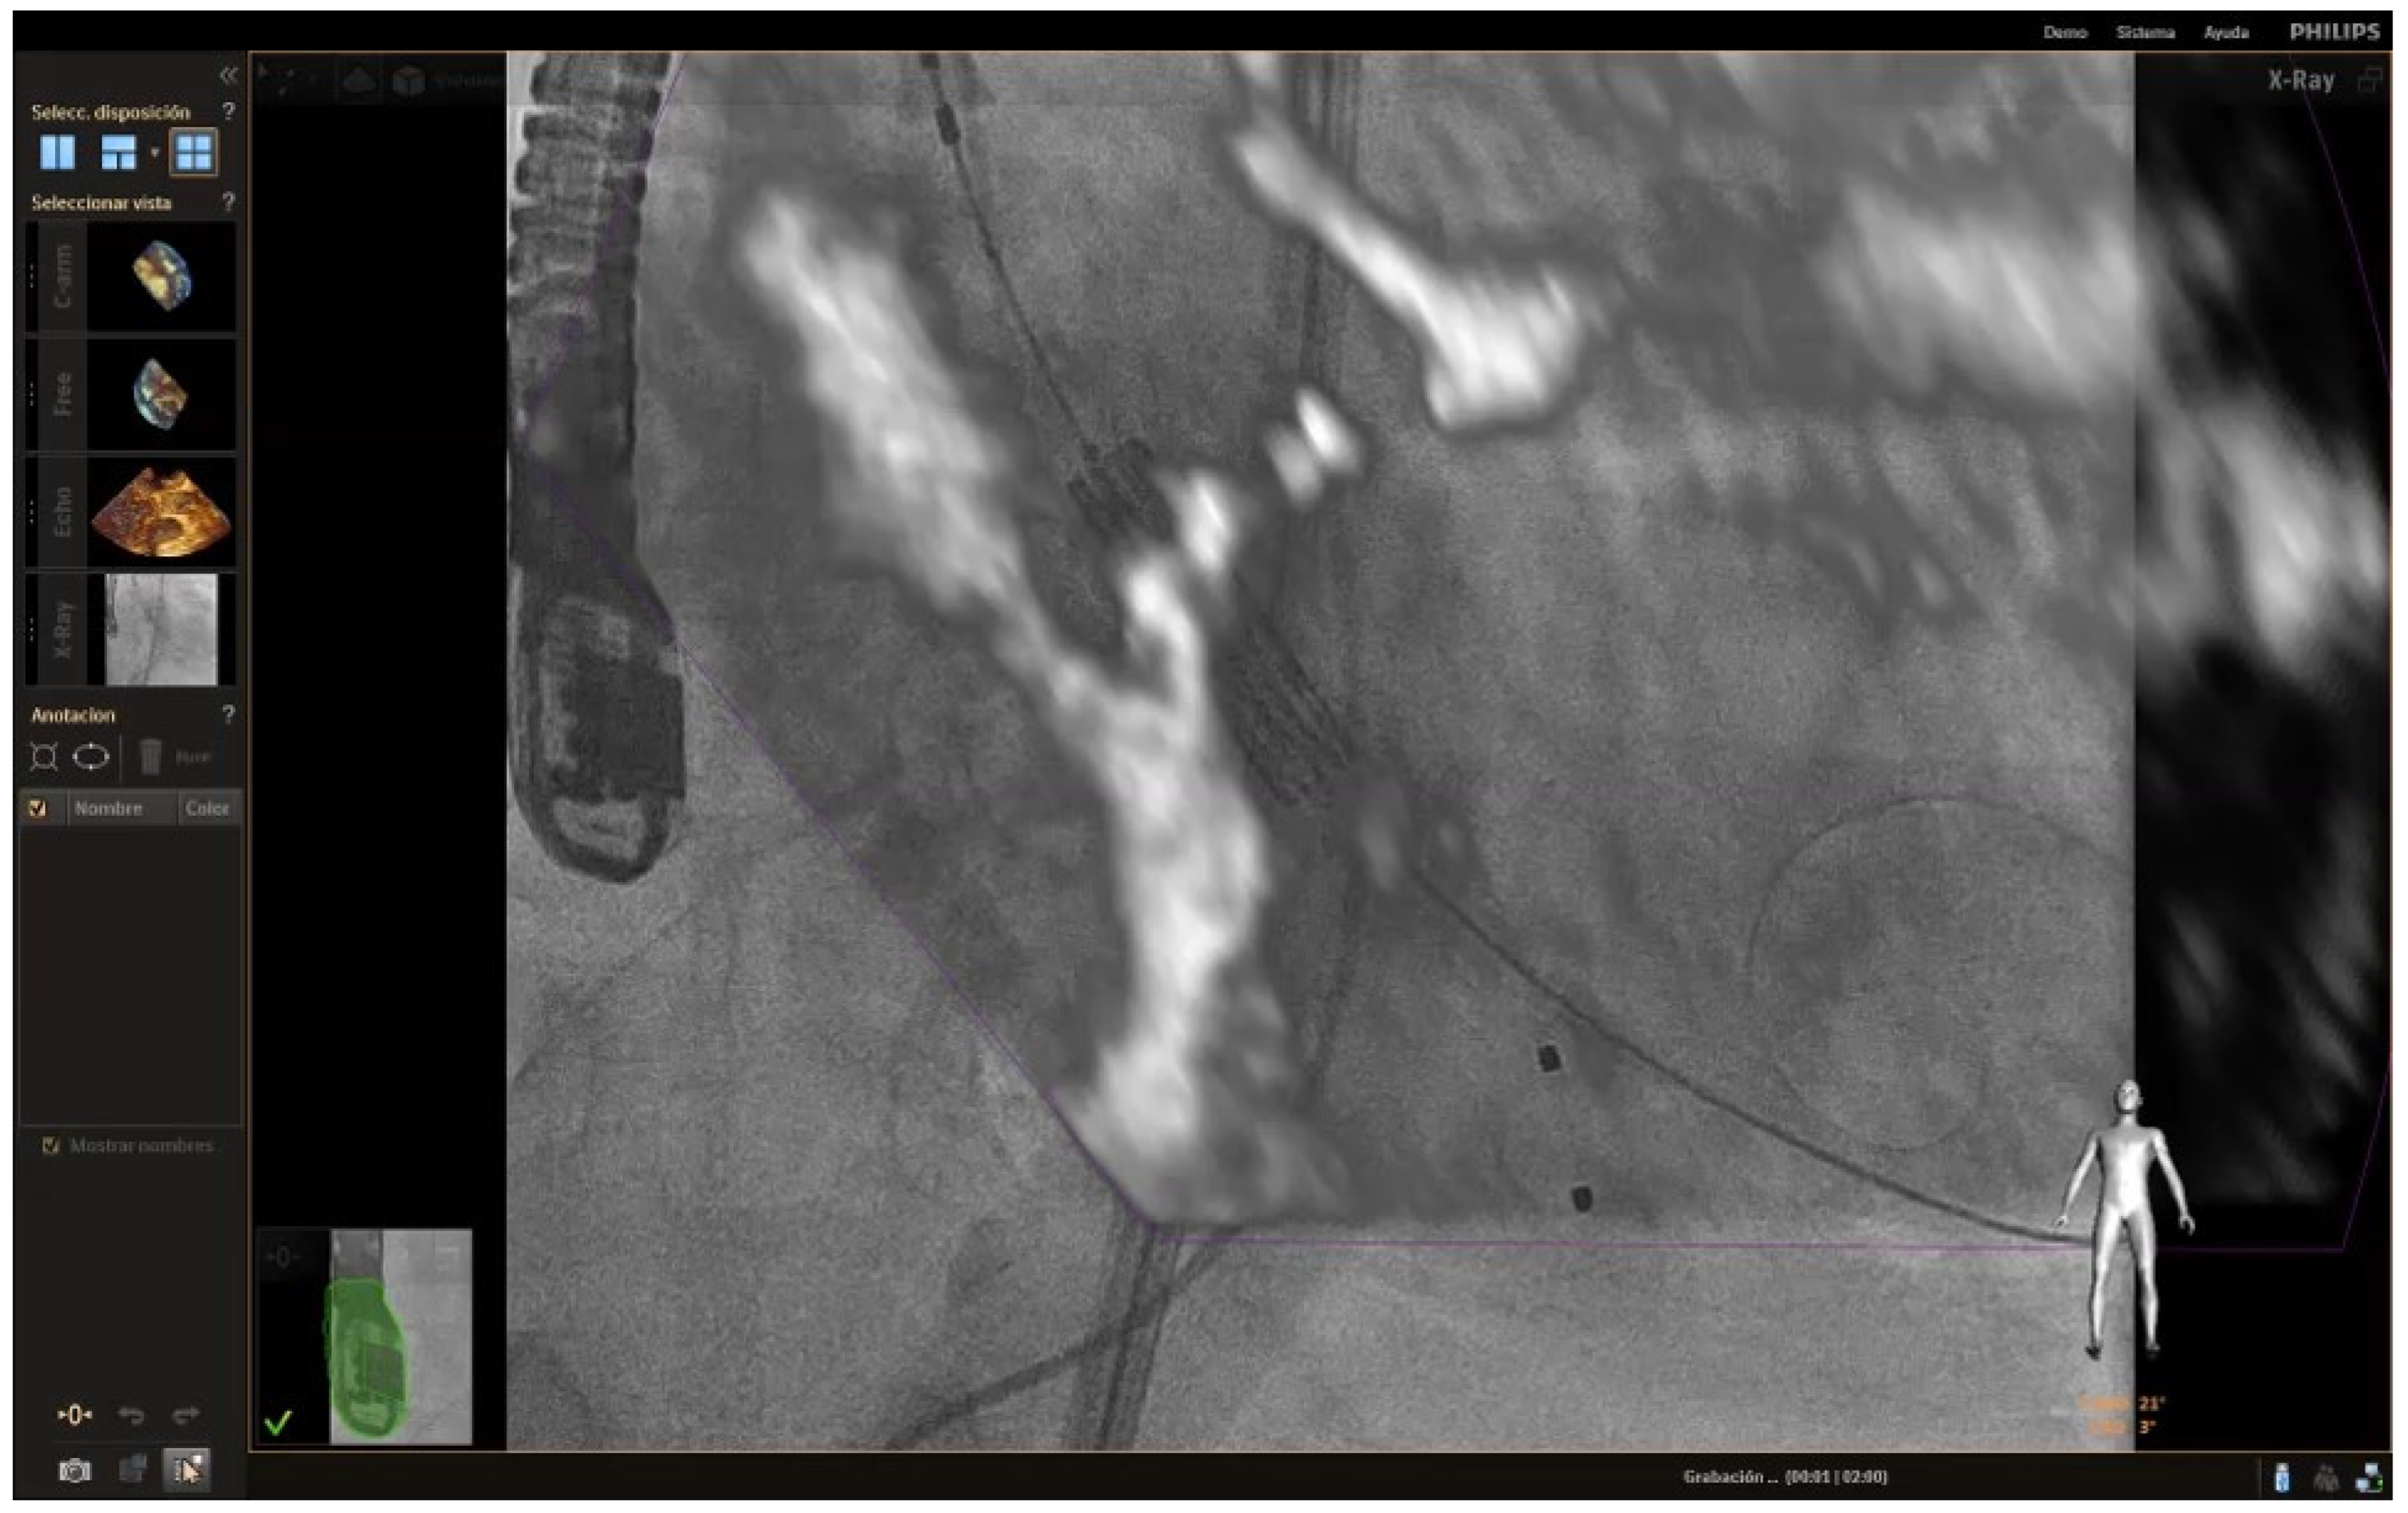

| 6 | The combination of the new microprobes and the new fusion techniques, which allow the fluoroscopy and the echocardiogram image to be seen simultaneously, will provide the opportunity to do the procedures much faster and more safely for the patient. |